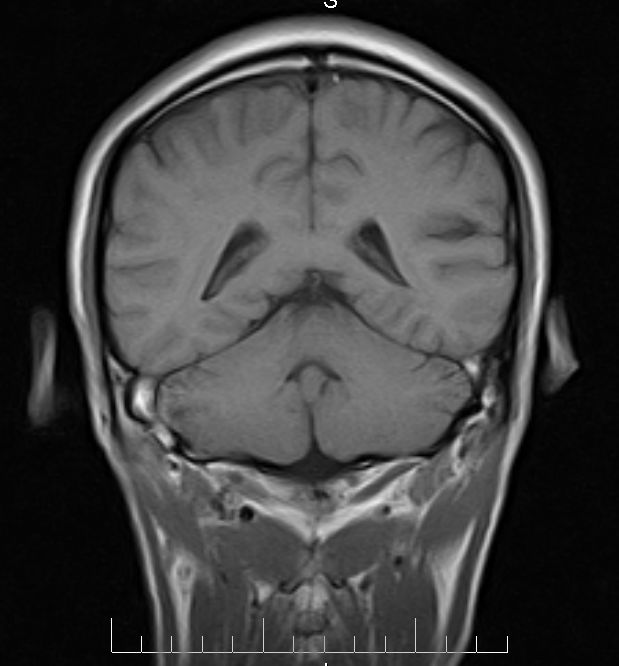

标题: MRI2379:30岁,男,癫痫10年,请各位看一下;CT示:左颞叶钙 [打印本页]

左颞叶区见不规则点状混杂信号影

支持2楼 左颞叶区见不规则点状混杂信号影,考虑动静脉畸形。

考虑左侧颞叶脑血管畸形(avm)。----t1低等高混杂信号,t2等高信号周边较多流空血管影[冠状位明显],mra左侧大脑中动脉受压,远侧聚集.